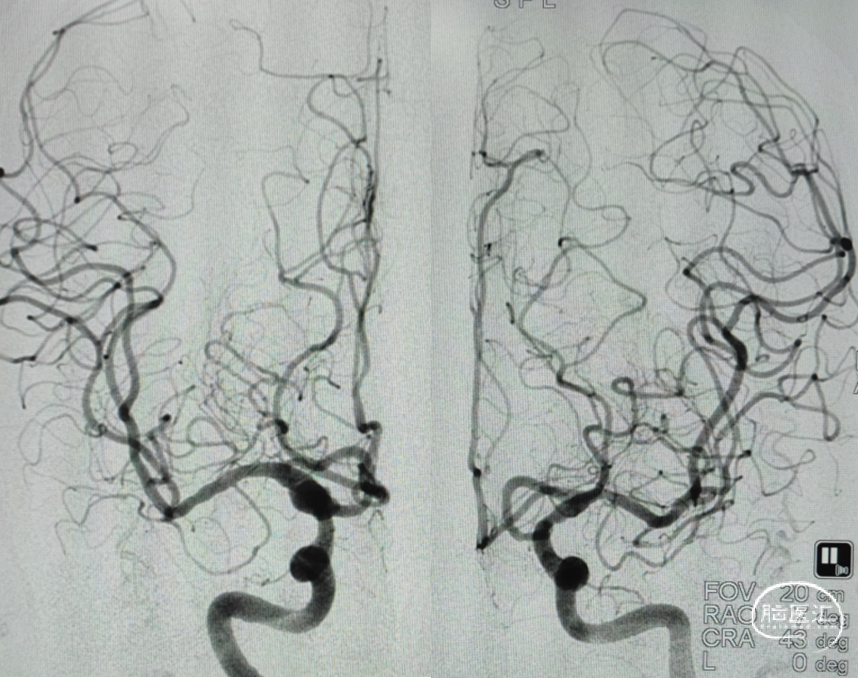

DSA:后交通动脉瘤

手术预案:后交通动脉瘤T支架辅助栓塞